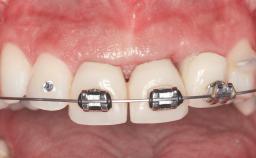

Replacement of Four Incisors with a Fixed Partial Denture on Two Narrow-Neck Implants after Implant Failure

| Interim Prosthesis during Healing | Removable Removable |